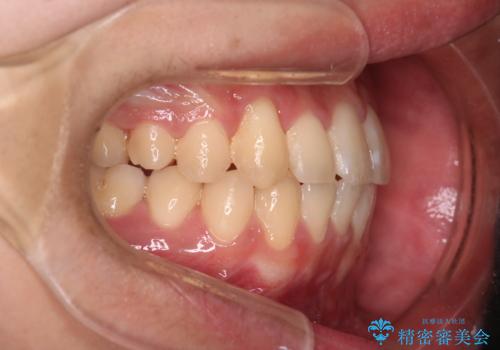

【クリア装置】八重歯とがたつきを綺麗に

- 上の八重歯と下の歯のがたつきを主訴に来院されました。

気にされていた八重歯とがたつきが綺麗に改善されました。